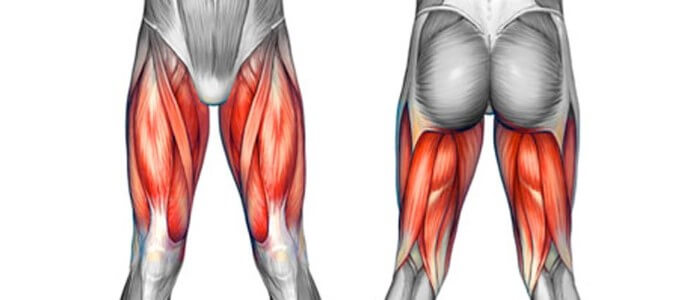

Nie tylko złamania mogą powodować ból. Naciągnięcia i skręcenia mięśni przy kości udowej również mogą być bolesne. Zazwyczaj ból pojawia się podczas ruchu, ale może być również odczuwalny w spoczynku. Lód, odpoczynek i unikanie obciążających ruchów zwykle pomaga.